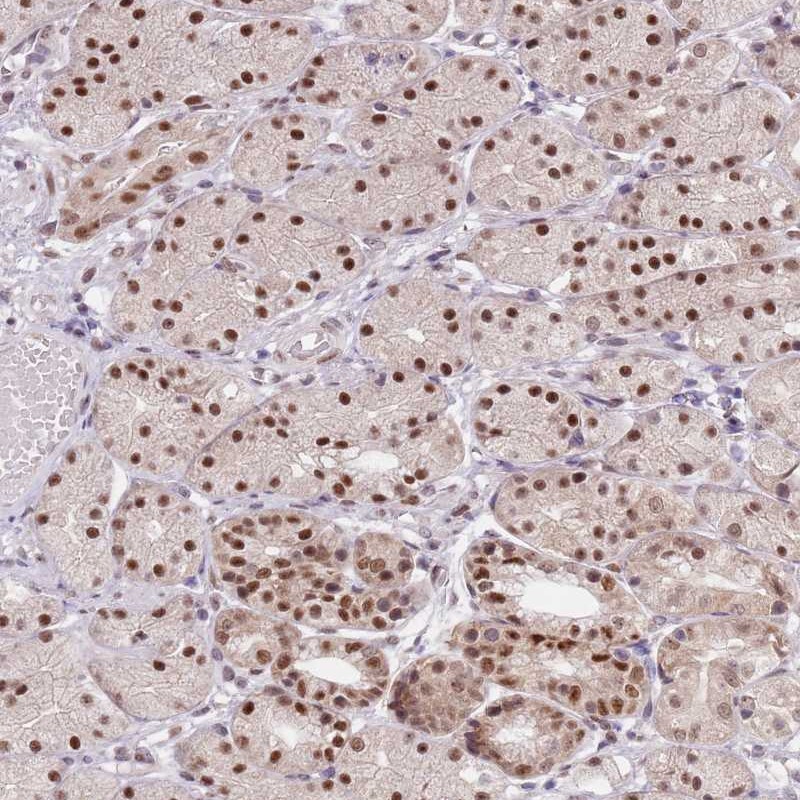

Immunohistochemical staining of human stomach, upper shows strong nuclear positivity in glandular cells.